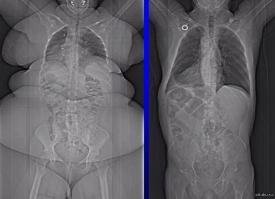

Пугающие рентгеновские снимки мужчины, которые весит 400 килограмм и является одним из самых тяжелых людей в мире. Вы только представьте себе на минутку, насколько структура тела этого толстяка по своему строению отличается от среднестатистического мужчины с атлетическим телосложением. Жесть.